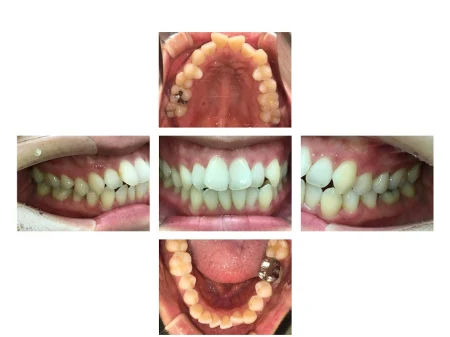

拝見すると、上下左右の前歯12本(中切歯/1番・側切歯/2番・犬歯/3番)がでこぼこに生えている「叢生(そうせい)」でした。

叢生の状態は見た目が悪いだけでなく、歯磨きがしづらいため磨き残しが出やすく、虫歯や歯周病にかかるリスクが高まります。

患者様は「なるべく歯を抜きたくない」とご希望でした。

患者様のご希望に沿い、非抜歯で可能な限り叢生と前歯の前突感を改善するために、奥歯を含めた歯並び全体の矯正治療に適しているマウスピース型矯正装置「インビザラインフル」を選択しました。

歯の後方移動をしっかり行うことで、前歯の突出感の改善に努めました。